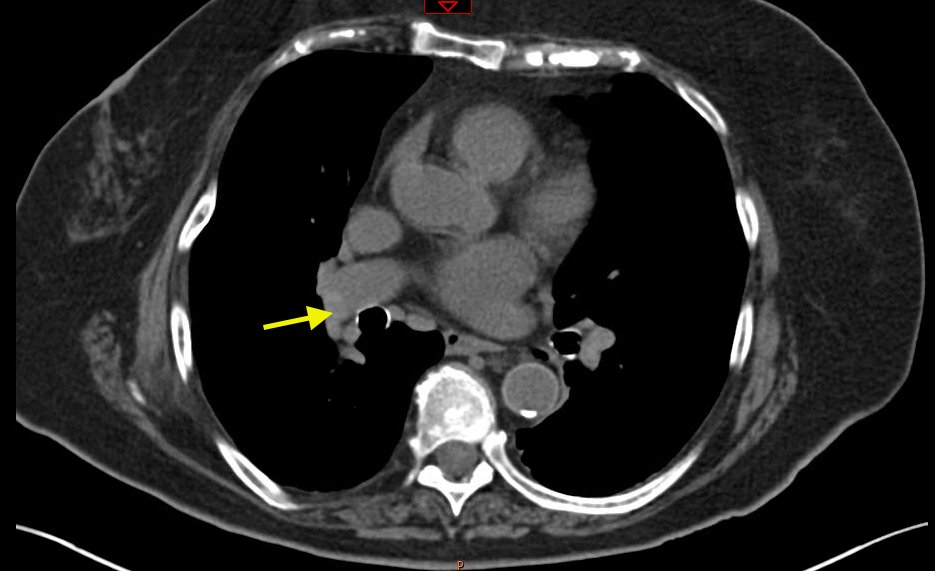

PE, Non-Contrast CT. Image 2. JETem 2017

Pulmonary Embolism: Diagnosis by Computerized Tomography without Intravenous Contrast